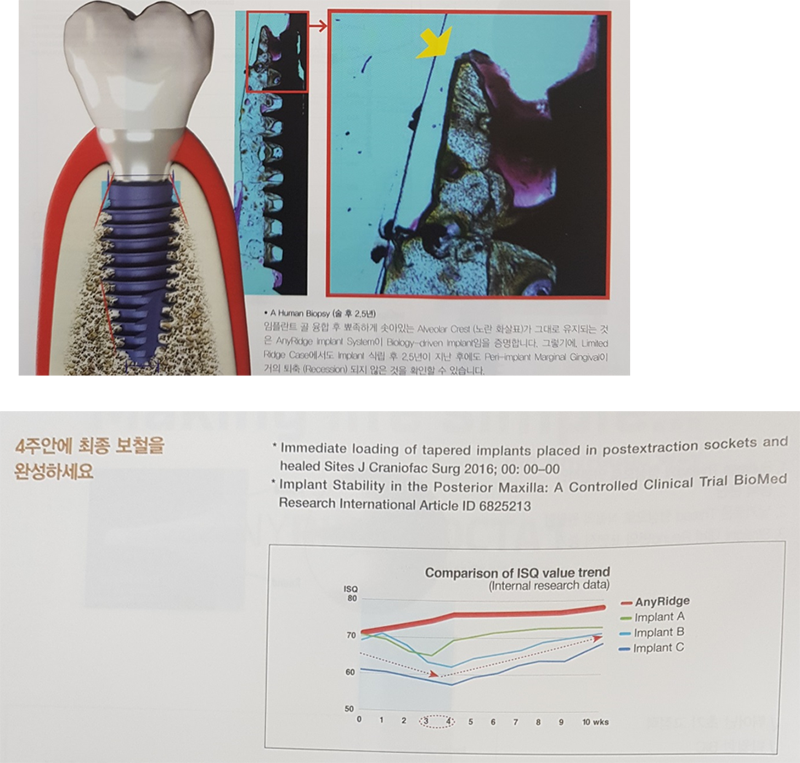

임플란트는 cortical bone 손상을 최소화 하기 때문에 초기고정이 매우 좋다.

즉시부하가 가능하다는 말이다.